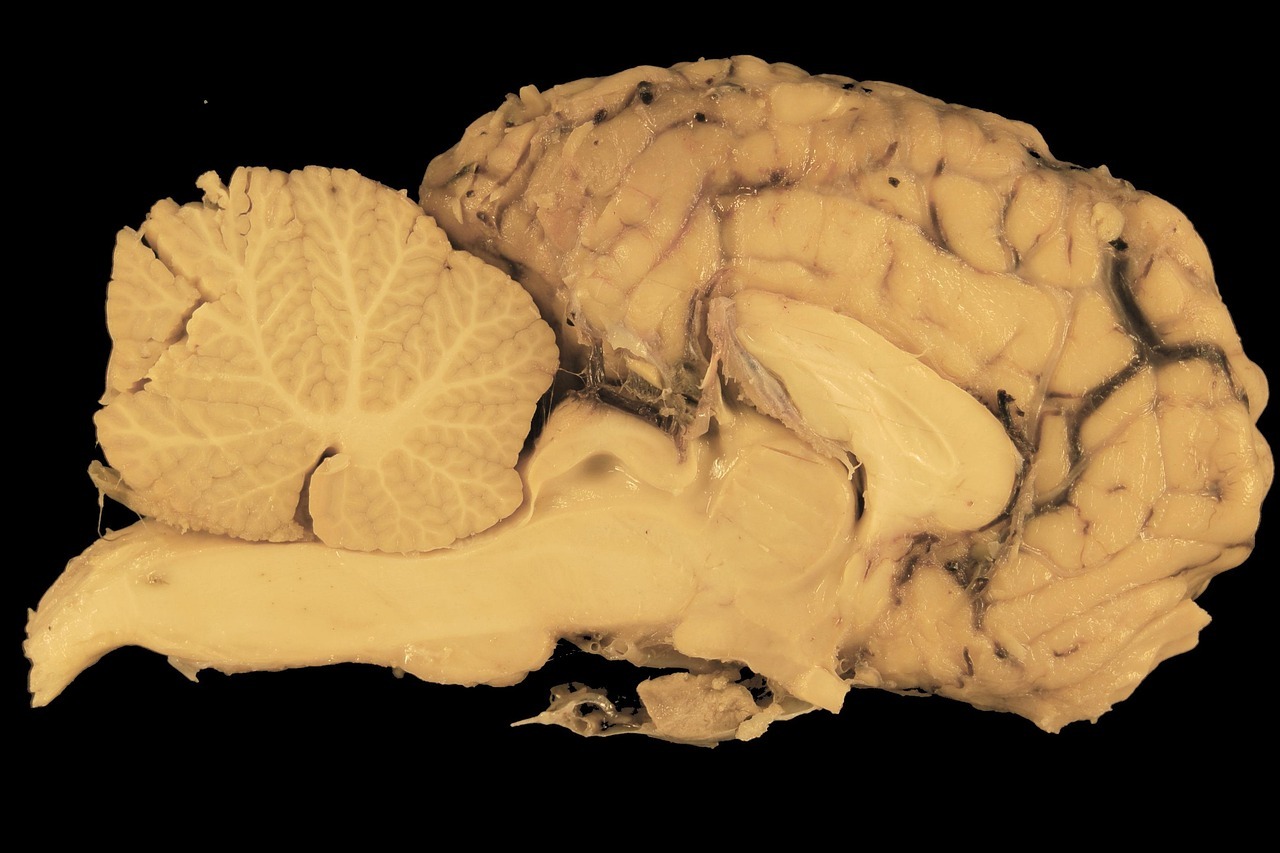

Alcune patologie neurologiche sono ictus, demenze, epilessia, neuropatie, Parkinson e tumori cerebrali. Molte di queste condizioni possono essere prevenute o trattate, ma le cure rimangono spesso fuori portata. Nei paesi a basso reddito e nelle aree rurali, la carenza di neurologi e strutture specializzate impedisce diagnosi rapide e trattamenti continuativi.